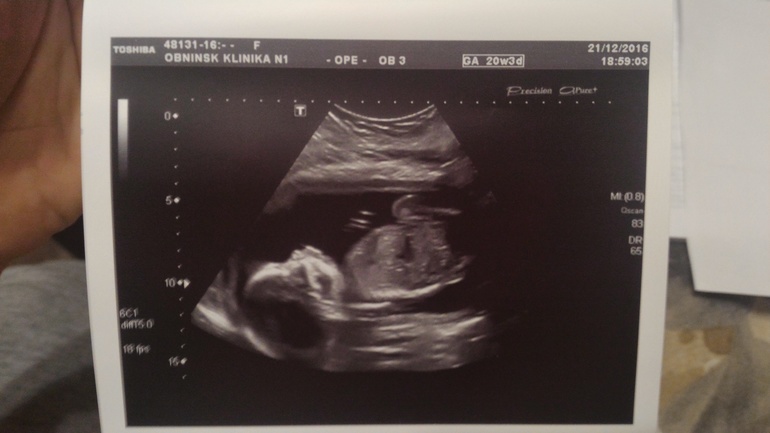

Сегодня 20 недель начались с похода на скрининг))) Нам там подтвердили сынульку, все с нами ттт хорошо, отклонений не выявлено по узи ставят 20+5 неделек) БПР -49мм , написали один живой плод в головном предлежании, плацента расположена по передней и задней стенкам левому ребру, лежим мы поперек маминого животика и я это прекрасно чувствую, буянит сын) головка справа,попка слева ))) Кол-во вод в норме шейка матки 39 мм)

В общем все хорошо и я счастлива) По состоянию все гуд, иногда только тянет связки по бокам, и то что он вытягивается когда лежит поперек доставляет дискомфорт конечно, но не такой уж и сильный) А так все замечательно)) ну и вот наш профиль и засняли нам наше достоинство)) и фотопузик)))